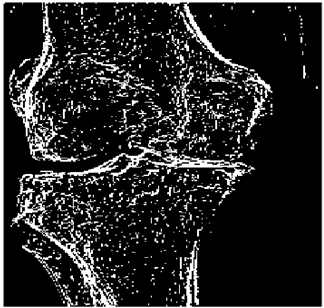

Table 5. X-ray Images.

X-ray 1X-ray 2X-ray 3X-ray 4X-ray 5

Mathematics 10 02421 i004 Mathematics 10 02421 i005 Mathematics 10 02421 i006 Mathematics 10 02421 i007 Mathematics 10 02421 i008

For the purpose of simulation, we consider two sets of images: (1) three images from MATLAB repository (Table 4) and (2) five X-ray images available online (Table 5).

Table 10 shows the following:

• In all cases, the Canny edge detector detects more edge pixels than both fuzzy compositions.

• As the level of noise increases, Canny and standard composition become adversely affected by the noise, and still more edges are detected by Canny; however, most of the detected edges by Canny are misdetections due to the impact of noise. As is obvious from this table, the smooth composition provides a better image with reduced noise density.

• In all cases, the PFOM value for the smooth composition is always greater than the PFOM value for the standard composition, according to Table 6.